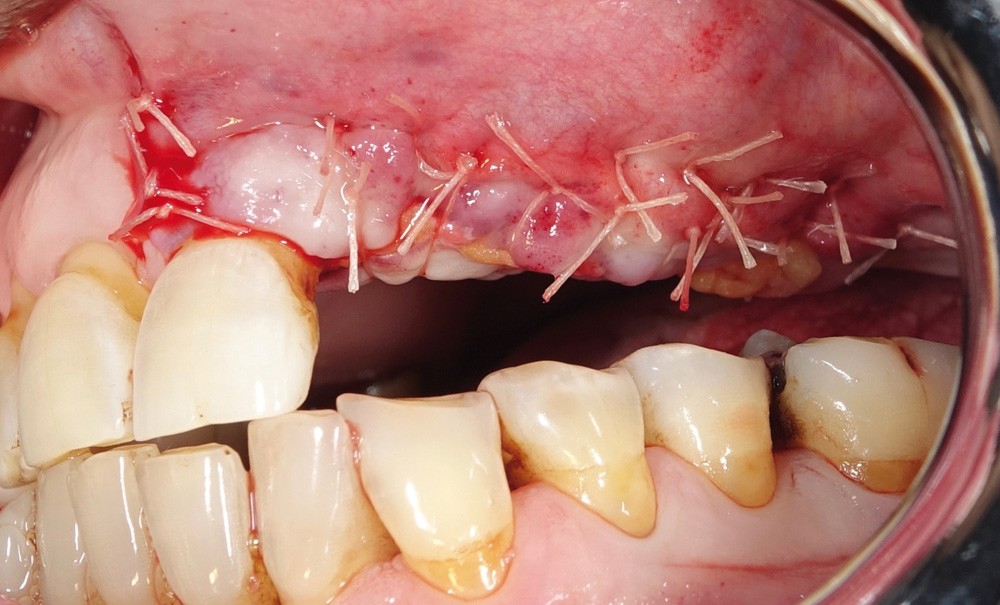

Les différentes techniques d’augmentation du volume osseux en vue de la pose d’implants dentaires ont pour objectif de recréer une architecture osseuse alvéolaire propice à la revascularisation des greffons. Les prélèvements osseux endo-buccaux ont notre préférence, car ils peuvent être réalisés sous anesthésie locale et sont mieux acceptés par les patients. De plus, la quantité d’os disponible au niveau de ces sites permet de reconstruire de grandes pertes de substance [5-7]. Les facteurs favorables au succès d’une autogreffe osseuse sont la stabilité initiale du greffon, la fermeture muqueuse sans tension et le maintien de la vascularisation [8]. Plusieurs études ont montré une meilleure incorporation des greffons lorsque le site de prélèvement et le site receveur avaient la même origine embryonnaire [8, 9].

L’objectif de ce travail est de présenter trois techniques d’augmentation osseuse verticale. En effet, il n’a pas pour vocation de décrire exhaustivement toutes les techniques d’augmentation du volume osseux. Ainsi, les techniques d’augmentation sous-sinusienne ne seront pas abordées. De même pour les techniques de régénération osseuse guidée par membrane résorbable ou non résorbable armée qui peuvent également être intéressantes pour les corrections de défauts verticaux de…